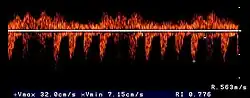

The ultrasound examination allows morphological changes in the kidneys in more detail. In addition to changes in size and shape, renal cysts, localized (focal) organ damage, water sac kidneys and urinary retention as well as tumors can also be visualized. Hardly defined (diffuse) organ changes are accompanied by changes in echogenicity, but can only rarely be assigned to defined diseases.[22] Pulsed Wave Doppler" can also be used to detect circulatory disorders.[23] Calcification (nephrocalcinosis) is also common in chronic kidney disease and can also be detected sonographically.[24]